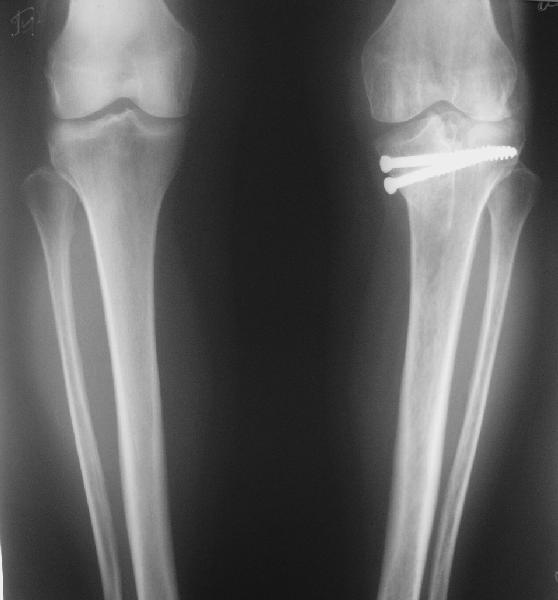

В отделение поступила  пациентка из области, 68 лет.

Травму получила год назад, находилась на лечении  в ЦРБ по поводу перелома

внутреннего мыщелка большеберцовой кости, была вот так прооперирована.

Имя     : get_image1.jpg

Тип     : image/jpeg

Размер  : 24344 байтов

Описание: отсутствует

Url     : http://weborto.net:8080/pipermail/ortho/attachments/20090921/92017f40/attachment-0002.jpg